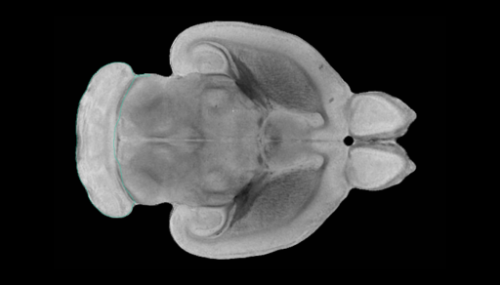

• jhet5570310231.pdf